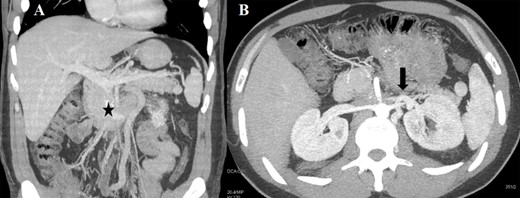

Case 1 was a 33-year-old male affected by a right testicular germ-cell tumor with enlarged retroperitoneal lymph nodes surrounding the infrarenal IVC. The patient underwent orchifunicolectomy and subsequent chemotherapy based on bleomycin, etoposide and platinum. A restaging computed tomography (CT) scan showed partial response and confirmed residual tumor involving both the IVC (with occluding thrombus) and the distal left renal vein (LRV) (Fig. 1A). CT scan also showed an efficient venous collateral pathway through the azygos−lumbar system (Fig. 1B), with no clinically evident lower limb edema. The patient underwent an en-bloc resection of the tumor mass with infrarenal IVC and LRV ligation without nephrectomy; no IVC prosthetic replacement was carried out. Recovery from surgery was uneventful with the exception of transient mild renal failure treated conservatively and without the need for dialysis. Renal ultrasonography showed regular bilateral parenchymal perfusion, and doppler ultrasonography of the lower limbs confirmed normal superficial and deep venous outflow. The patient was discharged 9 days after surgery. Histology showed a teratoma with alpha-fetoprotein expression and extensive post-chemotherapy areas of necrosis.

(A) CT scan (coronal section) of the retroperitoneal mass (asterisk) involving the IVC and LRV with congested gonadal vessels; (B) cross-section CT scan showing well-represented collateral outflow (arrow) of the renal–azygos–lumbar system.